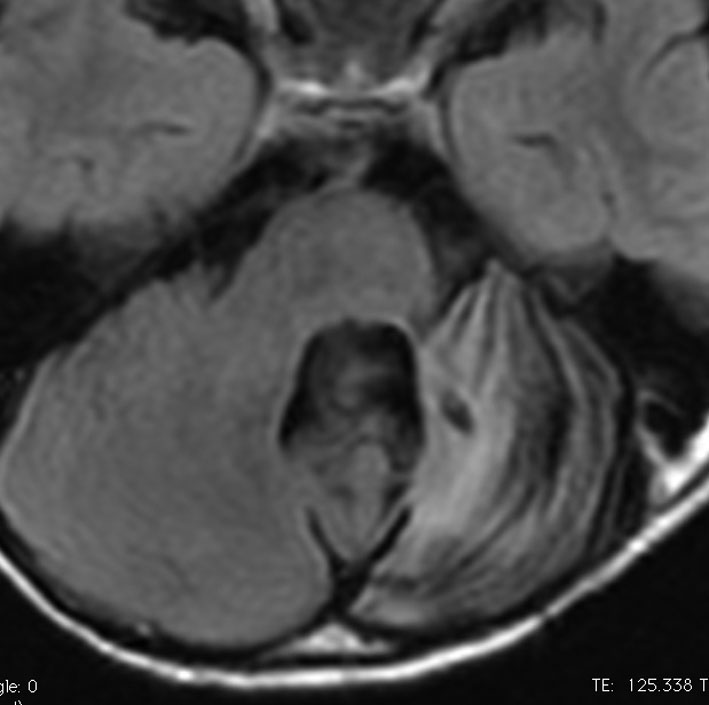

3歳の髄芽腫です。発症時から小脳表面や小脳橋角部を含めて転移がありました stage M2。化学療法で腫瘍はかなり縮小して,3歳7ヶ月まで頑張ってから,後頭窩照射 25.2グレイ14分割と脳脊髄照射 CSI 28.8グレイ16分割の放射線治療をしました。当時このような例では,脳脊髄照射 36グレイが標準治療でしたから,これでもかなり線量を落としました。

左側の画像は照射後4ヶ月目です。延髄の左側に放射線壊死が生じました。これは数ヶ月かかってゆっくり消褪しました。右側の画像は照射後1年くらいのものです。大脳白質にびまん性に萎縮性変化がみられます。典型的な放射線治療による白質萎縮です。この程度の線量でも脳壊死や全脳萎縮を生じない子どももいます。